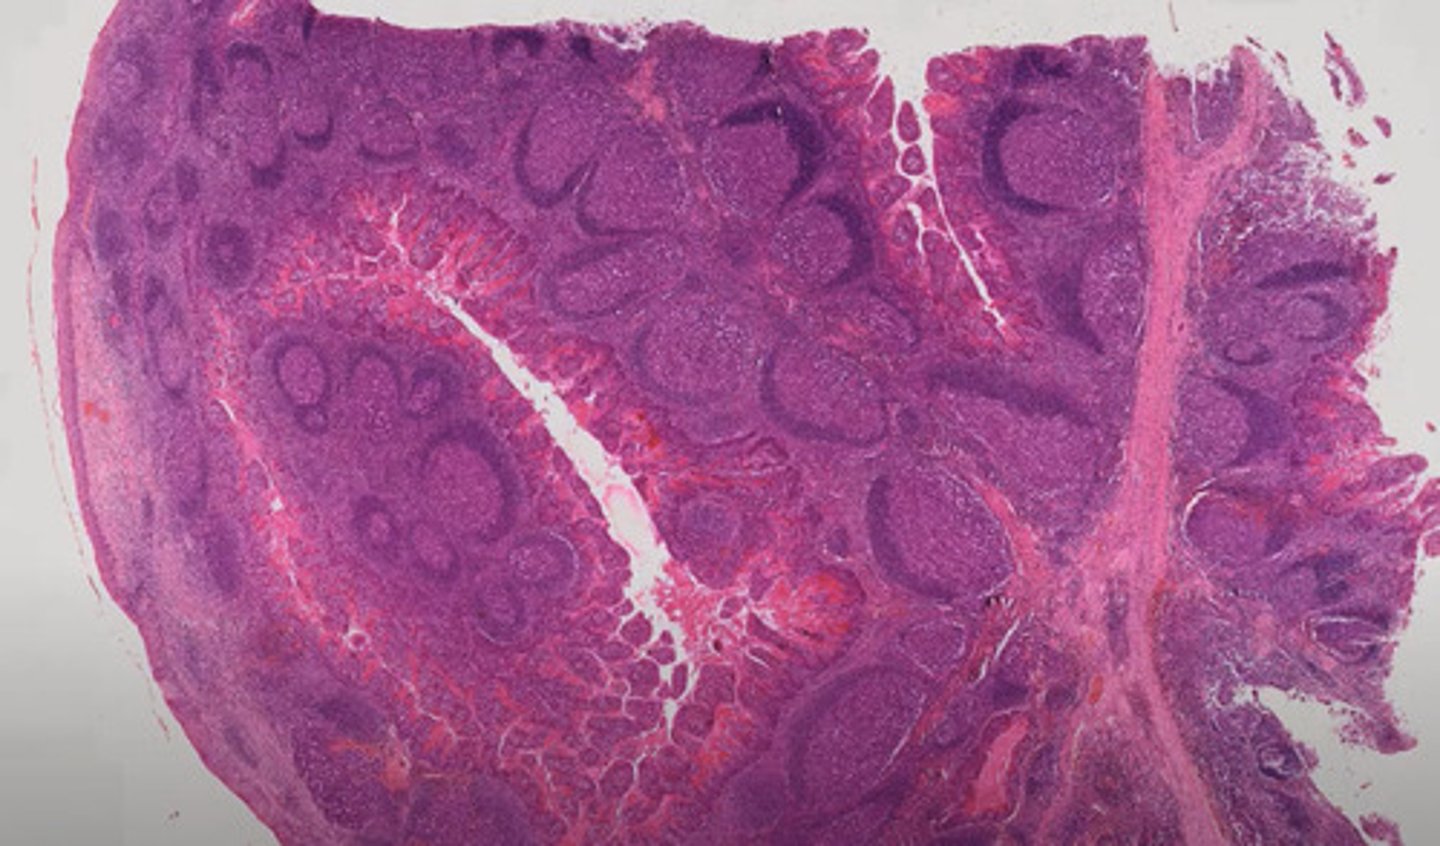

Jelito grube (H+E)

Wyrostek robaczkowy (H+E)

Jelito cienkie - dwunastnica (H+E)

Jelito cienkie - kręte (H+E)